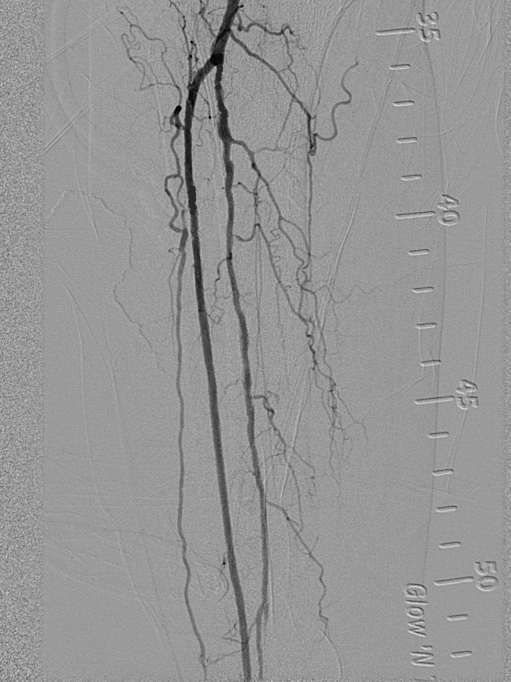

图4

膝关节下血管闭塞

图3为术前DSA,图4为术后DSA